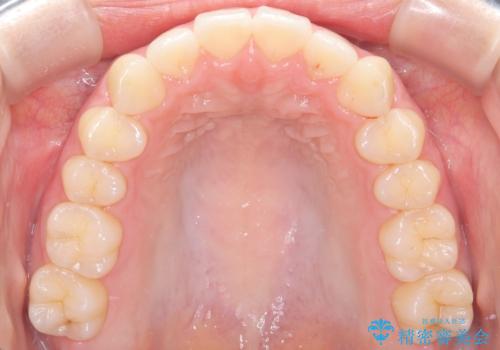

下顎前歯の叢生を短期間で改善

- 患者様は、下顎前歯のガタガタ(叢生)の改善を希望して来院されました。診断の結果、非抜歯で治療可能であると判断し、透明で目立たないインビザラインを使用する矯正治療計画を立案しました。短期間での治療を希望されていたため、IPR(歯間削合)を併用してスペースを確保しながら、効率的に歯を並べることを目指しました。

治療では、インビザラインを用いて計画的に歯を移動させ、短期間での歯列改善を実現しました。IPRを行うことで、抜歯をせずに必要なスペースを確保し、歯列全体を整えました。治療中は、装置の適切な装着時間を守ることが重要であり、患者様にも継続的な協力をお願いしました。また、歯肉や歯根への負担を最小限に抑えるため、歯の移動を慎重に管理しました。結果として、短期間で下顎前歯の叢生を改善し、自然な見た目と機能性を兼ね備えた歯列を実現できました。